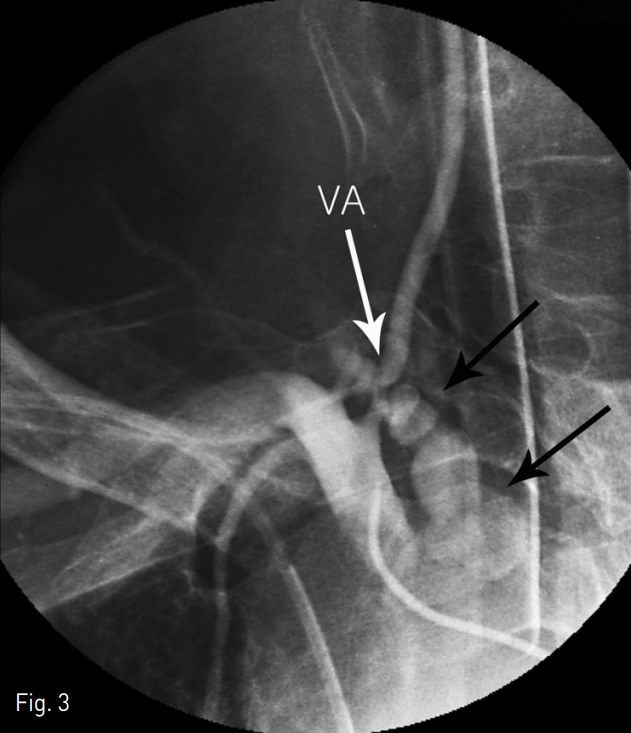

환자는 인터벤션 시술실에서 응급 혈관조영술을 실시하였고 우측 쇄골하정맥 직상부 우측 척추동맥에서 발생한 큰 가성동맥류가 확인되었다. 또한, 좌측 척추 동맥이 잘 유지된 것을 확인하였다. 4 Fr 혈관촬영용 도관 (JB2, Cook, Inc .; Bloomington, IN, USA)을 척추동맥으로 넣은 후 가성동맥류 원위부부터 두 개의 5mm, 한 개의 4mm 금속코일 (Nester, Cook)로 척추동맥을 색전한 후 10mm x 25mm 풍선확장형 스텐트 그라프트 (Jomed International AB, Helsingborg, Sweden)을 척추동맥 기시부에 걸쳐서 우측 쇄골하 정맥에 위치시켰다.

Fig. 3

Selective right subclavian angiography shows the irregular shaped large pseudoaneurysm (black arrows) of the proximal portion of the right vertebral artery (VA)